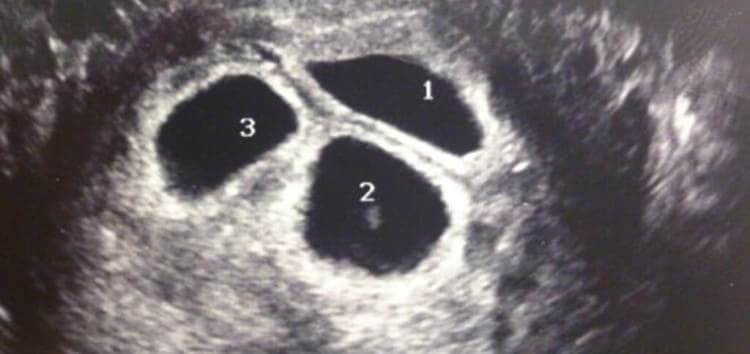

Sarah and Andy couldn't believe what they heard and they took some time to absorb the thrilling news. As they were involved with previous mothers, they were also there for the third mother at every step. They got super excited when the third mother invited them to an ultrasound appointment.

At the appointment, the couple saw their new child for the very first time. However, the scan showed something else that surprised everyone. The birth mom was actually carrying three babies instead of one.

Not One, Two, But Three Babies

The birth mother, doctor, Sarah, and Andy were completely shocked when they saw there were three heartbeats on the ultrasound monitor. They didn't lose hope when the first mother decided to keep the baby, they remained resilient when the second mother also decided to keep her baby and they were expecting just one bundle of joy. But they didn't know that the universe was planning on making up for previous chances that didn't deliver the results the couple wanted.